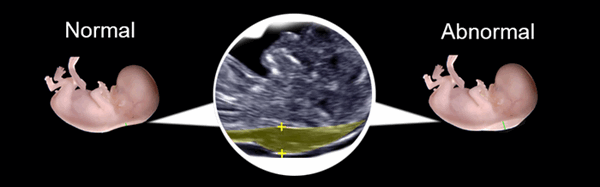

Сравнение нормальной и ненормальной толщины воротникового пространства